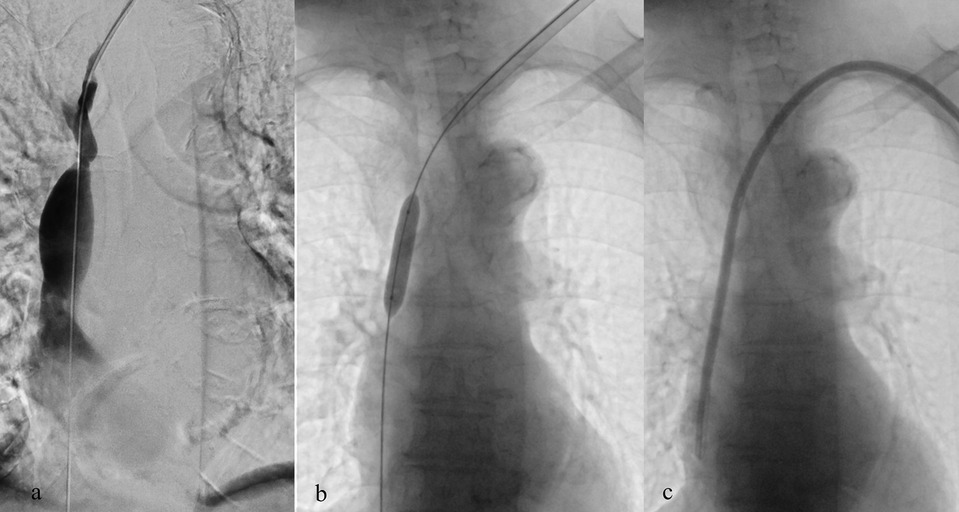

Background: Tunneled cuffed catheter (TCC) remains a crucial vascular access option for patients undergoing hemodialysis, particularly in those who are not candidates for arteriovenous fistulas or grafts. However, placement carries immediate and delayed complications. Objective: This narrative review aims to provide a comprehensive overview of the complications encountered during and after the placement of a TCC for hemodialysis, highlighting current evidence, risk factors, prevention strategies, and management approaches. Methods: A critical selection of relevant literature was performed through PubMed and Scopus databases, focusing on articles published in the last two decades. Particular attention was given to studies reporting on mechanical, infectious, thrombotic, and late-onset complications, as well as technical factors influencing outcomes. Results: Complications of TCCs can be classified as immediate (e.g., arterial puncture, pneumothorax, bleeding), early (e.g., catheter malposition, exit-site infections), and late (e.g., central venous stenosis, catheter-related bloodstream infections, thrombosis). Patient-and procedure-related factors increase risk. Ultrasound and fluoroscopy, strict sterility, and timely management reduce complications rates. Conclusion: TCCs are indispensable in selected patients, but understanding their complications is key to patient safety and outcomes. Optimal outcomes depend on accurate patient selection, operator expertise, and standardized post-placement care.